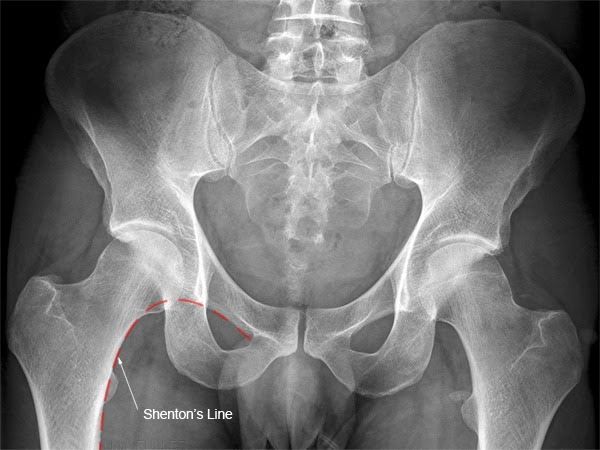

불완전 골절일 경우 MRI 나 골주사 검사를 활용할 수 있습니다.[X-ray 상 고관절 골절의 확인]

Shenton's line*이 지켜졌는지 중요합니다.

외회전되면서 소전자가 더 도드라집니다.

Femur neck/head 비대칭이 관찰됩니다.

골절 라인의 경화증(하얗게 보입니다)

골 균질의 이상이 관찰됩니다.

골절 주변부 영상은 더럽게 보입니다.

*Shenton’s line

대퇴골 경부(femoral neck)의 medial과

Superior pubic ramus의 아래 라인인

Shenton's line이 예쁜 곡선을 그려야 합니다.

만약 이 라인이 깨지면 대퇴골 경부가

부러졌다는 의심을 하게 됩니다.

그러나 모든 대퇴골 경부 골절이

Shenton’s line이 깨지게 만드는 것은 아닙니다.